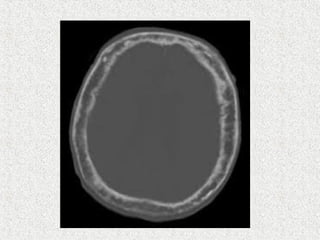

 Skull

 Circumscribed patch of osteoporosis in skull

 Osteoporosis circumscripta

 Cotton wool appearance

 Mixed

 Diploic widening

 Tam o'Shanter sign

 frontal bone enlargement, with the appearance of the

skull falling over the facial bones, like a Tam o'

Shanter hat

 Skull  Circumscribedpatch of osteoporosis in skull  Osteoporosis circumscripta  Cotton wool appearance  Mixed  Diploic widening  Tam o'Shanter sign  frontal bone enlargement, with the appearance of the skull falling over the facial bones, like a Tam o' Shanter hat